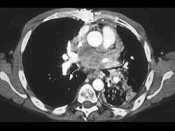

单项选择题男,45岁, 咳嗽,咯血2月余, 有20余年吸烟史,请结合影像学检查, 选出最可能的诊断 ( )

A、肺结核

B、小细胞肺癌

C、肺脓肿

D、肺囊肿

E、肺错构瘤